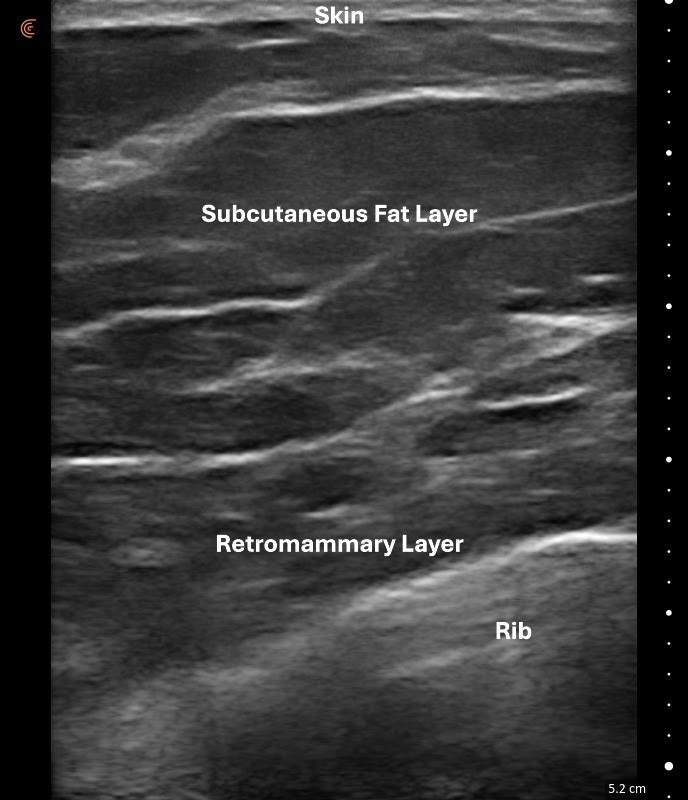

Women are diagnosed with dense fibrous breast tissue based on the balance between two main types of tissue in the breast. One type is glandular tissue, which is the working part of the breast, and the other is the fatty layer that sits just under the skin.

When a woman has more glandular tissue than fatty tissue, her breasts are considered dense. Density can vary—some women have moderately dense breasts, while others have extremely dense breasts.

In the ultrasound image of a dense breast, you can clearly see that the glandular tissue layer is larger than the fatty layer. The image also shows that the ultrasound probe (called a transducer) can see all the way down to the ribs, which confirms that every layer of the breast has been examined. Seeing the breast from the skin all the way to the chest wall is very important for a thorough evaluation.